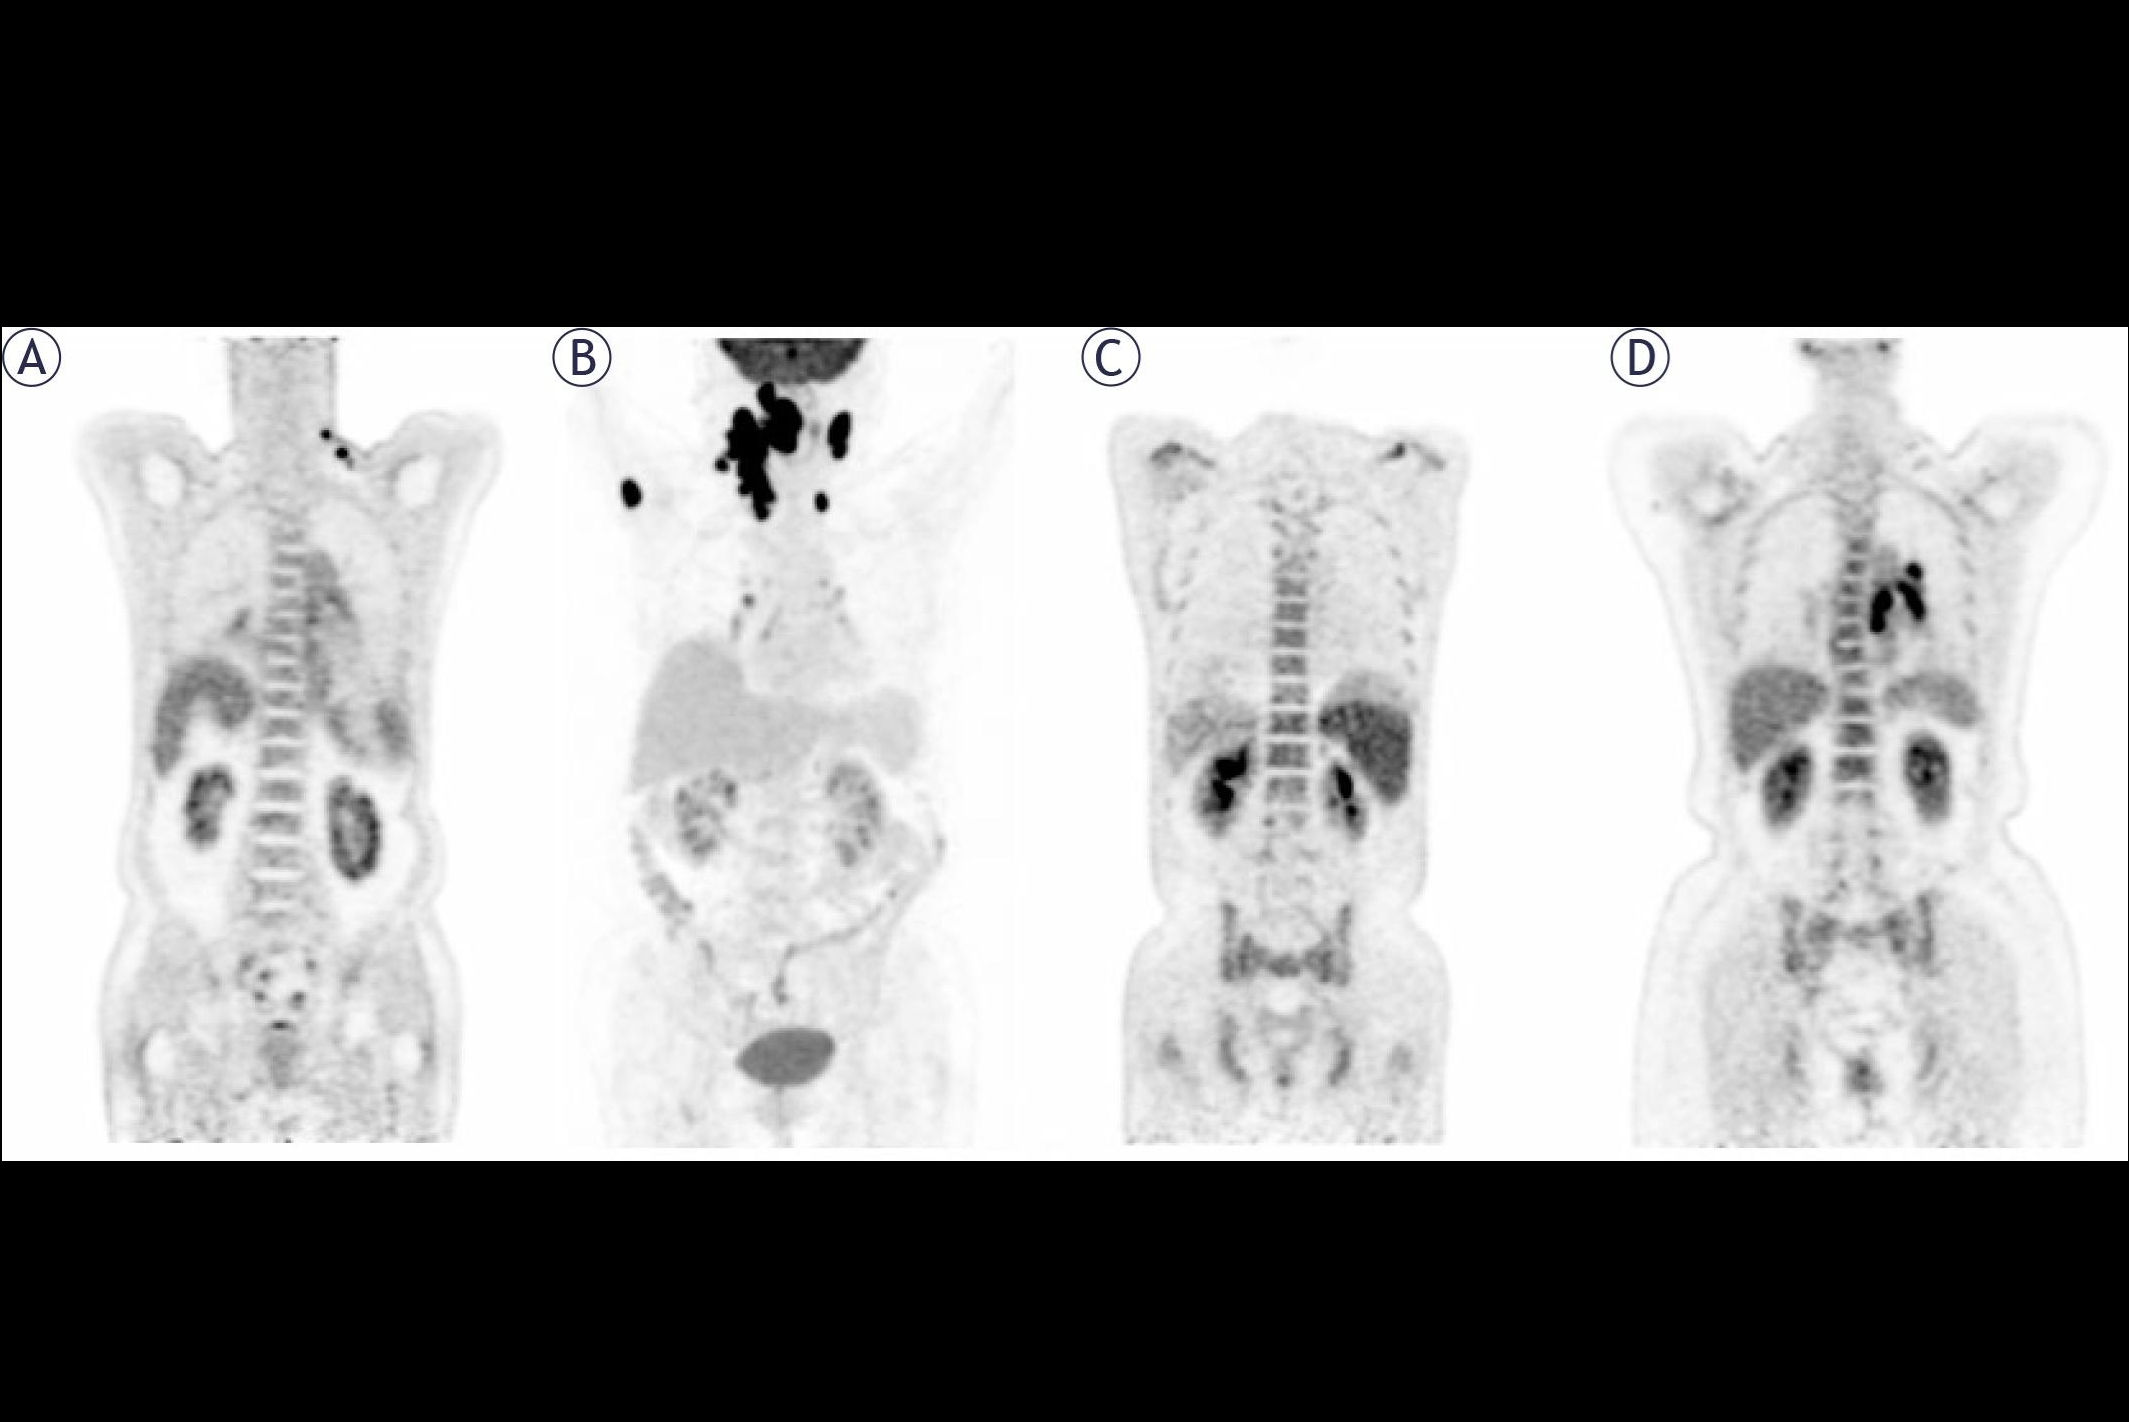

Diagnostic amyloid PET has been extensively studied since the first radiotracer was approved in 2012 by the U.S. Food and Drug Administration (FDA), MITA said. The procedure identifies amyloid plaque, one of the main characteristics of Alzheimer's disease. MITA said using amyloid PET is "clinically and fiscally responsible" by discouraging unnecessary drug use.